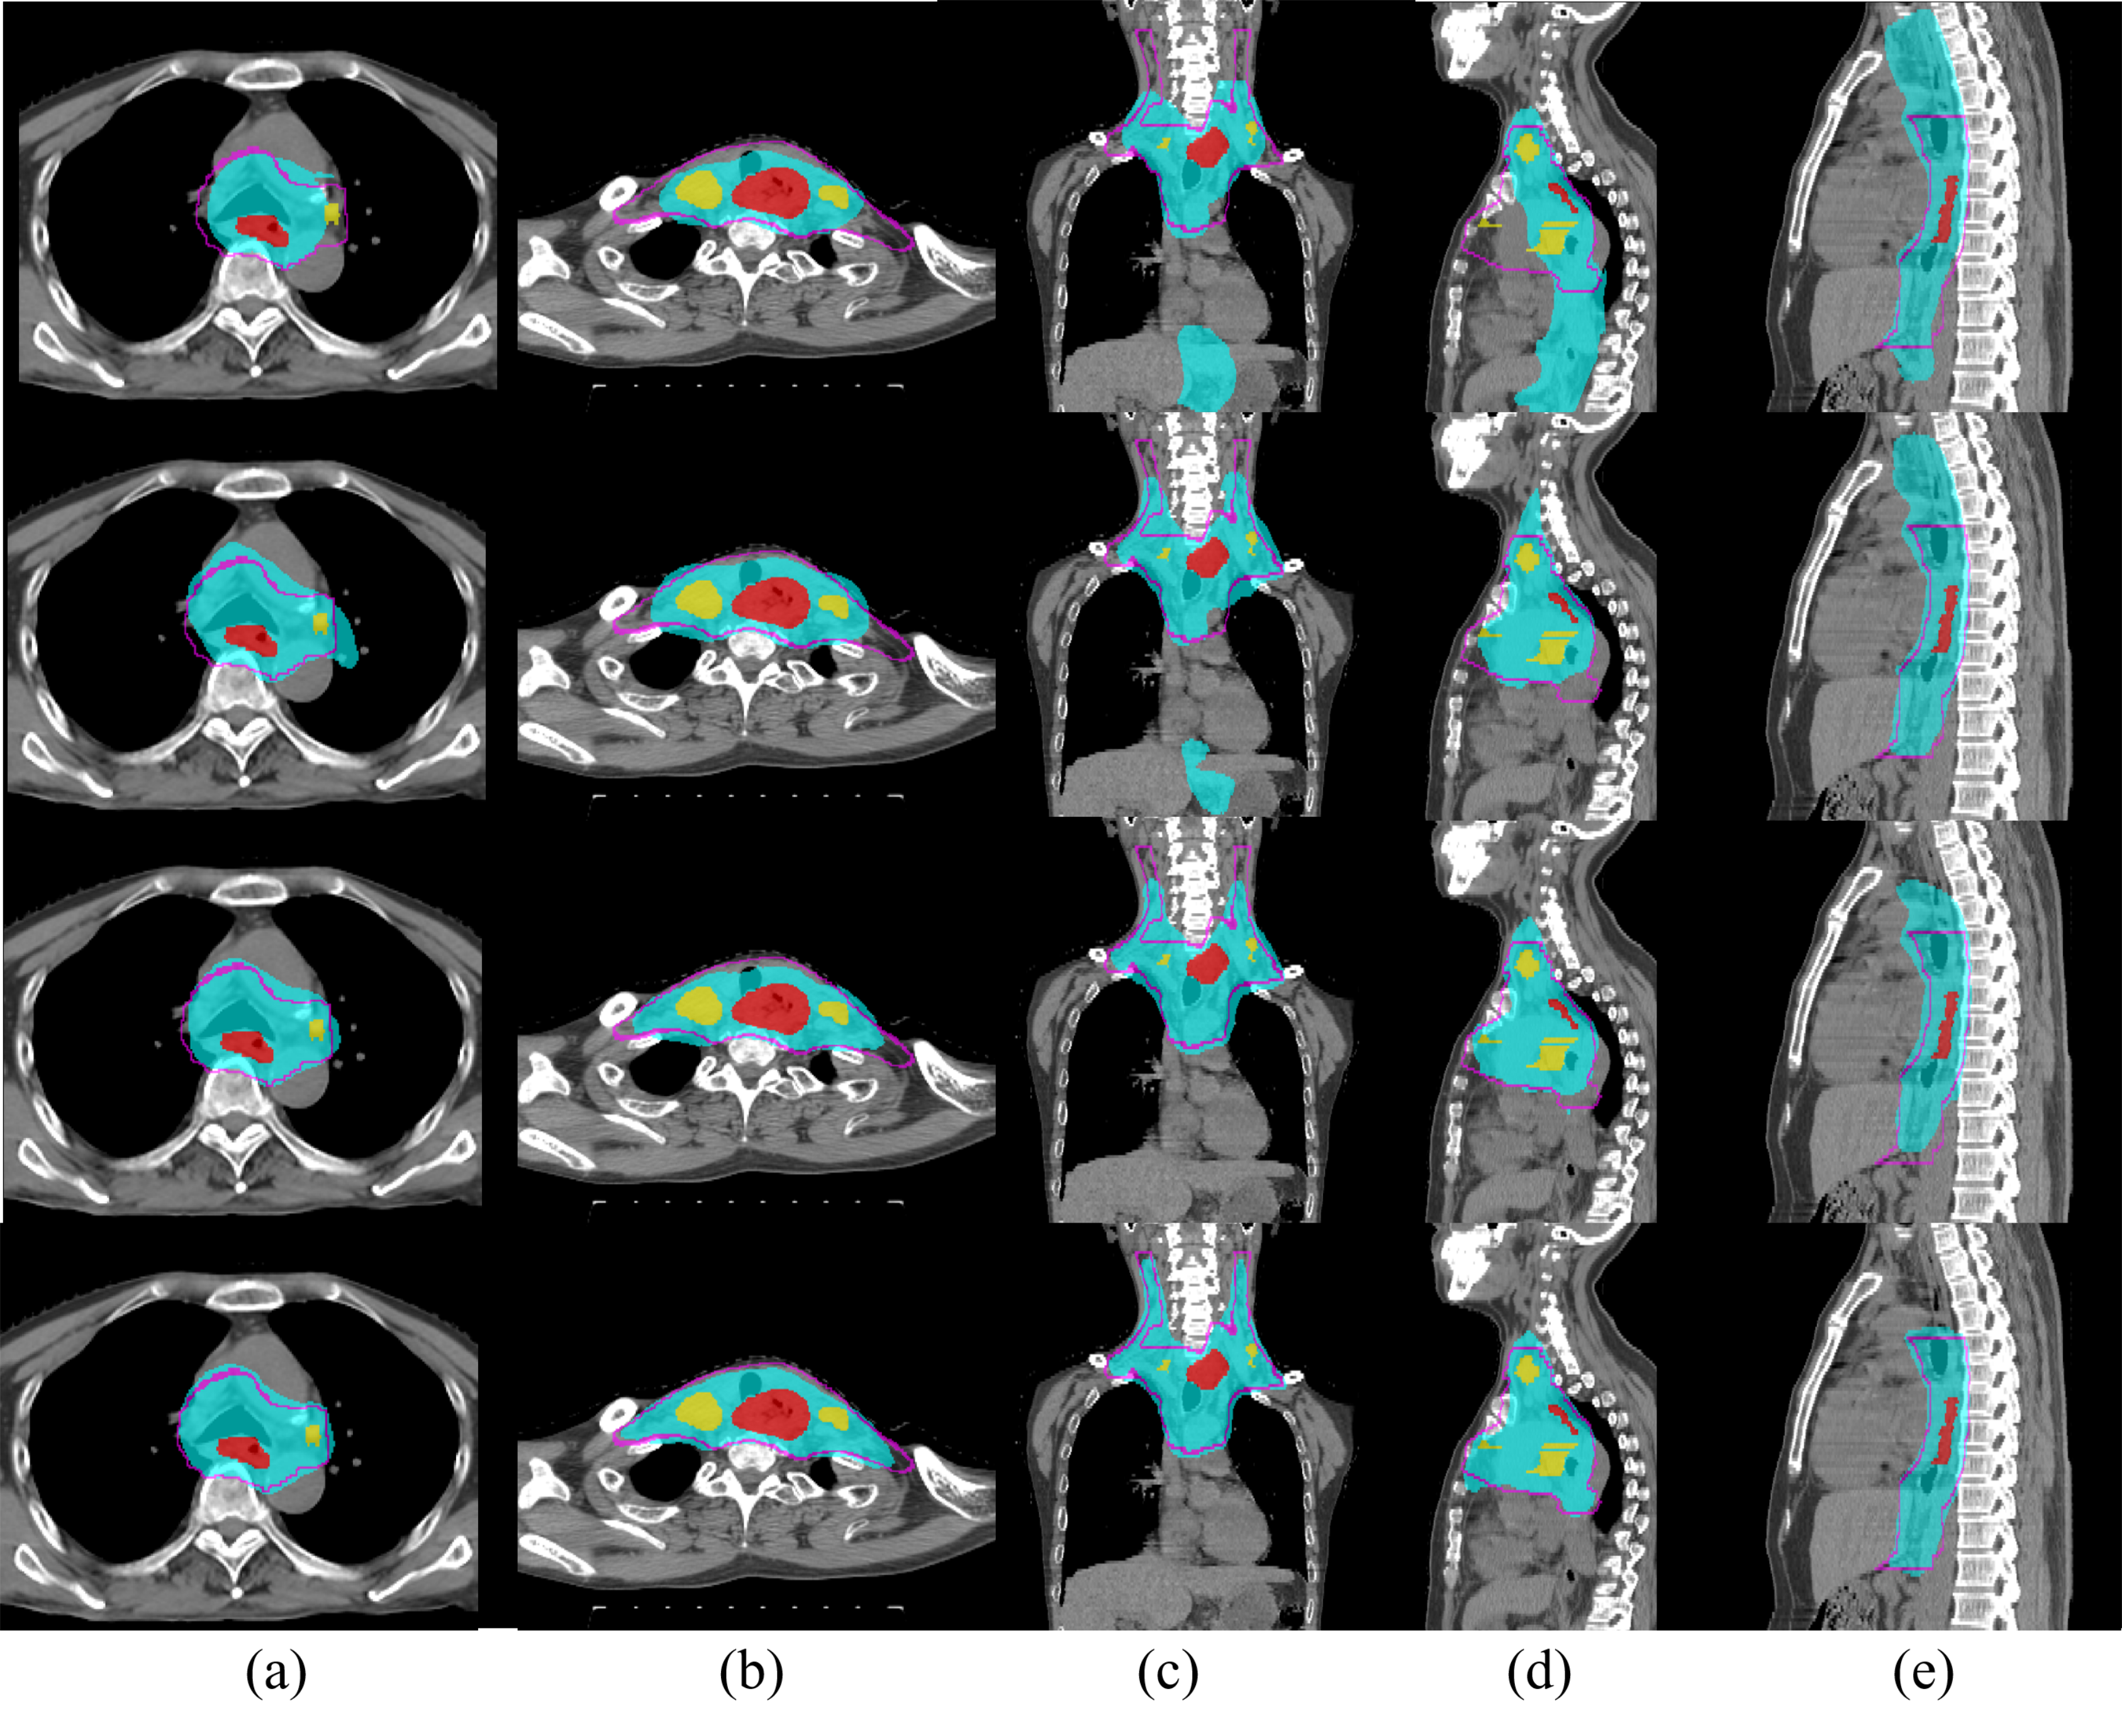

Refer to caption

Figure 3: Qualitative illustration of esophageal \acsCTV delineation using different \acPHNN setups. Red, yellow and cyan represent the \acGTV, \acLN and predicted \acCTV regions, respectively. The purple line indicates the ground truth \acCTV boundary. The 1stsuperscript1𝑠𝑡1^{st} and 2ndsuperscript2𝑛𝑑2^{nd} rows show examples from setups using pure \acRTCT [15] and when adding \acGTV/\acLN binary masks [3], respectively. The 3rdsuperscript3𝑟𝑑3^{rd} and 4thsuperscript4𝑡4^{th} row show examples when adding \acGTV/\acLN \acpSDT and our proposed \acGTV/\acLN/\acOAR \acpSDT, respectively. (a) and (d) demonstrate that the pure \acRTCT setups fail to include the regional \acpLN, while (c) to (e) depict severe over-segmentations. While these errors are partially addressed using the \acGTV/\acLN mask setup, it still suffers from inaccurate \acCTV boundaries (a-c) or over coverage of normal regions (d,e). These issues are much better addressed by our proposed method.